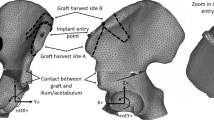

Cadaver pelvis was used to scan and build pelvis model. Artificial bone was used in lab testing. Sourcing of materials was from a dog that died of natural causes and the artificial bones from Sawbones Company (Sweden). Using 3D scanning a stl image was produced of a canine pelvis (25 kg male Collie breed) and this was subsequently refined in CAD. Using the CAD files, the images were imported in MSC Marc software to produce a working finite element (FE) model with 3 dimensional tetrahedral elements with linear shaped functions. The dimensions of a precontoured pelvic osteotomy plate with eight 3 mm screws and a twisted seven 3 mm screw straight plate were used to build the 2 fixations implants for the FE models. The screws were fixed to behave as unlocked screws. Before the FE simulations were run validation bench tests were carried out using artificial cancellous bone blocks (Sawbones, Malmo). Osteotomy and plate fixation were set up in the 2 methods: 1. Ventral plate fixation 2. Lateral plate fixation. The load required to cause a deformation of set amount was recorded for 3 experiments for each plate position. This data was used to validate the FE simulation for all configurations.

Finite Element (FE) models for each of the plate configurations studied were built to determine and verify the joint stiffness according to the applied load. Each of the FE models proposed that formed each configuration considered the osteotomised pelvis, the different plates and the screws. The geometric models used in the FEM discretization process of each of the parts (pelvis, plates and screws) were generated by measurements from actual samples of plates and artificial osteotomised pelvis. Due to the fact that the surface of the artificial osteotomised pelvis is very irregular; a 3d scanner was used to obtain its geometrical model. The remaining parts (plates and screws) were modeled directly in the FE MSC Marc software used. For all plate configurations studied, three dimensional FE models with 4-node isoparametric tetrahedral elements were used to mode the pelvis, plates and screws. An average element size of 0.6 mm was used for the cortical and cancellous bone, while for the plates and screws element sizes were for 0.8 mm and 0.9 mm respectively. An outer thin cortical bone and an inner cancellous bone were used to model the pelvis according to the literature. The material properties used for the cortical bone were E = 17,000 MPa and ν = 0.25, while for the cancellous values of E = 150 MPa and ν =0.3 were used. A titanium alloy with E = 107,000 MPa and ν = 0.34 was used for modeling of the plates and screws. The cortical and cancellous bone topography in the osteotomised area of the FE pelvis model was the same for all plate configurations (Fig. 1). A segment-to-segment method with a coefficient of friction of 0.1 was used for detecting mechanical contact between the plates and pelvis for all studied configurations. The mechanical contact between the screws and the osteotomised pelvis was defined via a glue contact between the matching nodes in both contact bodies. The same boundary conditions were applied in all finite element models in order to compare the different stiffness’s obtained. An equivalent load of 300 N was applied progressively on all FE models in order to facilitate its convergence. The load was applied in a distributed manner on the femur-hip joint contact area in order to simulate the actual behavior of the joint. The movement of the nodes that connected the pelvis to the column were constrained in order to immobilize the pelvis. Figure 2 shows a model of the pelvis which details the area where the load was applied and the area of the spinal column in which the constraint was applied.

In this study, two types of different plate configurations were studied. The first configuration studied was a DPO plate with eight screws on the lateral ilium. The final configuration studied was a ventral plate and was fixed to the pelvis with seven screws. In addition, a small gap in the osteotomised pelvis area was taken into consideration for all configurations studied in order to determine their influence on the stiffness of the joints. This gap is defined as the separation corresponding to a one angular degree (1°) between the different parts in which the osteotomised pelvis is divided. Figure 3 shows a configuration of plate in which the gap has been considered (Fig. 3a) and another in which it has not been considered (Fig. 3b).

Figure 4a shows the DPO plate mounted on the osteotomised pelvis. Four screws were used on one side of the osteotomy while another four screws were used on the opposite side (see Fig. 4b). The dimensions of the plate were 15 × 3 mm and the diameter of the screws was 3 mm. In this configuration, all screws pass through the entire pelvis, and mechanical contact between the plate & cortical bone and between the plate & screws is created in order to completely define the contact in the plate. Contact between the bone fragments is defined in the elements close to the osteotomy in order to detect when the osteotomy gap is closed or open.

Figure 5a shows the ventral plate mounted on the osteotomised pelvis. Four screws were used on one side of the fracture while three screws were used on the opposite side (see Fig. 6b). The dimensions of the plate were 6 × 2 mm and the diameters of the screws were 3 mm. Similar to the previous configuration, contact between the bone fragments is defined in the elements close to the fracture site in order to detect when the gap is closed or open.